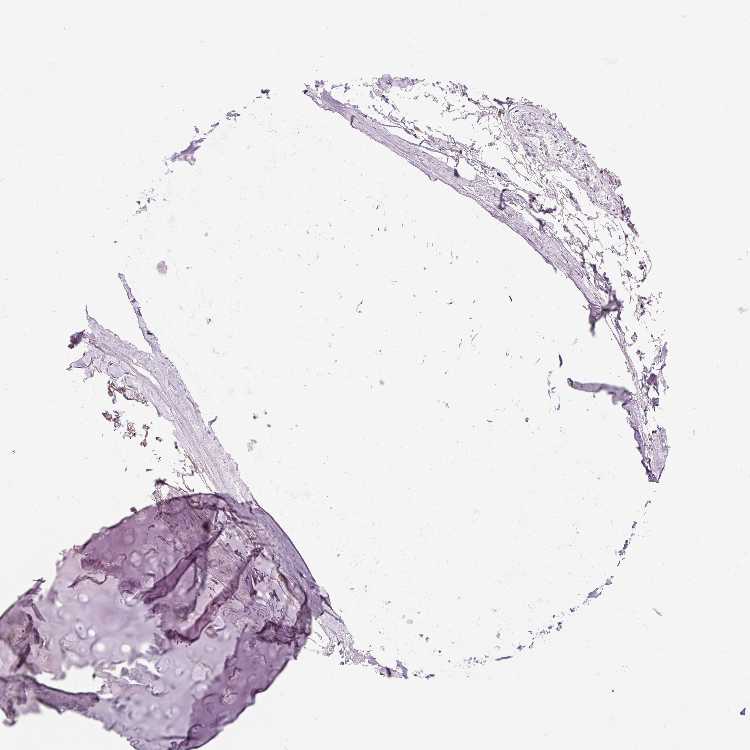

SOFT TISSUE 1 - Antibody stainingi

Antibody staining in the annotated cell types in the current human tissue is reported as not detected, low, medium, or high, based on conventional immunohistochemistry profiling in selected tissues. This score is based on the combination of the staining intensity and fraction of stained cells.

Each image is clickable and will lead to virtual microscopy that enables deeper exploration of all samples and also displays staining intensity scores, fraction scores and subcellular localization as well as patient and tissue information for each sample.

Antibody HPA036503Antibody HPA064387Antibody HPA076072Antibody CAB020784

Chondrocytes Not detectedHighNot detected-

Fibroblasts Not detectedMediumNot detectedMedium

Peripheral nerve Not detectedLowNot detectedMedium